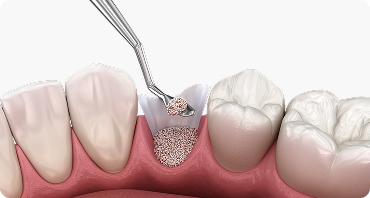

상악동 거상술

윗니 잇몸뼈의 두께가 얇을 경우, 상악동 막을 정교하게 거상하여

인공뼈를 보강하는 전문 시술입니다.

임플란트 식립을 위한

뼈 높이를 확보하여 장기적인 성공률을 높입니다.

상악동거상술

상악동 거상술은 치조골 높이 부족으로

임플란트 시술이 어려운 경우,

상악동을 이용하여 인공 뼈를 이식함으로써

임플란트 시술을 가능하게 하는 중요한 수술 기법입니다.

상악동 거상술 시행

부족한 잇몸뼈를 보완하여 임플란트

식립 환경을 안전하게 형성합니다.